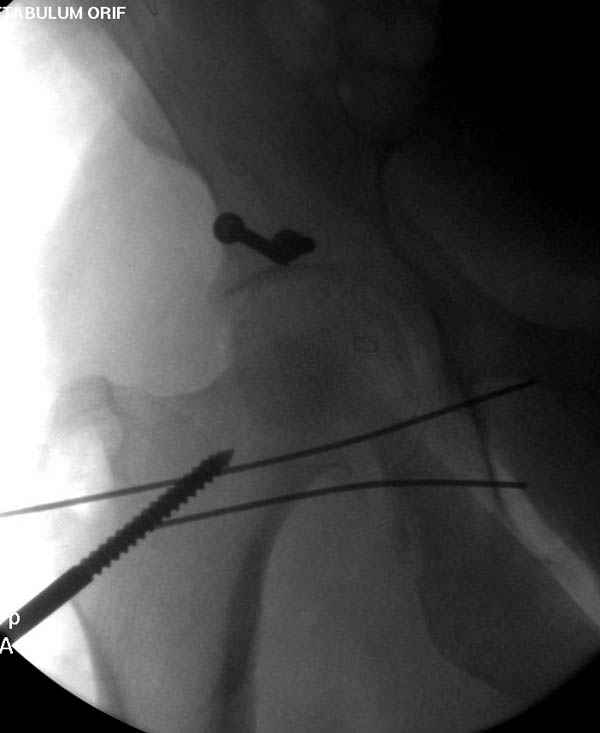

Наличие рентген контроля (ЭОП) помогает во время

репозиции и фиксации, но многие коллеги умудряются без рентгена фиксировать несколькими спицами перкутанно.

Наш недавний случай перкутанной фиксации "методом

Сиэтла" спицами 2.8 мм с резьбой на конце.